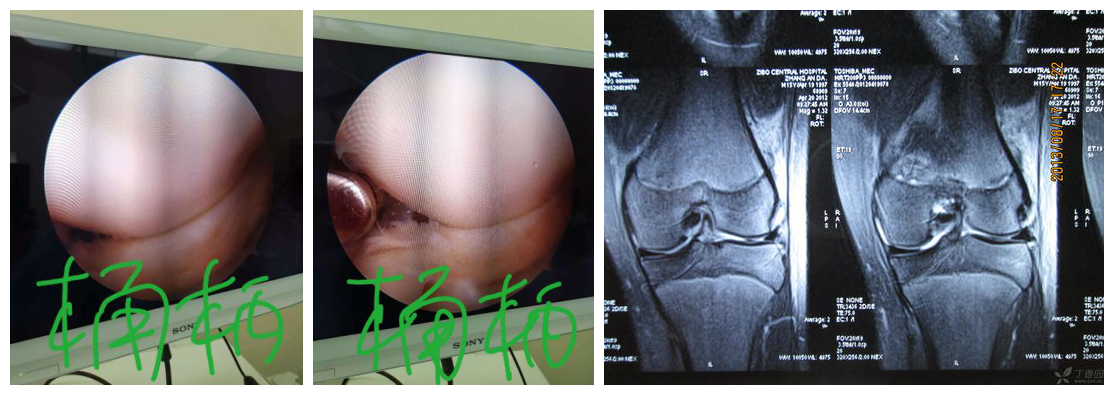

那么人们就会有疑问,半月板那么小,那么不起眼,怎么会引起膝关节绞锁呢,那是因为半月板三度损伤分为好几种类型,其中桶柄样撕裂卡在膝关节髁间窝,或大的纵裂和斜裂卡在股骨与胫骨关节就会出现绞锁症状。

2、膝关节软骨骨折:由膝关节外伤后引起,易漏诊,以髌骨关节内侧面发生率最高,为46.8%;其次为股骨外髁关节软骨面,发生率为31.5%,骨折后软骨骨折片脱落在关节腔内形成软骨游离体,可引起膝关节绞锁症状,此类疾病也容易出现临床漏诊。

5、剥脱性骨软骨炎:本病原因尚不清楚,目前有外伤学说及和内分泌遗传两种学说;好发16岁至25岁之间男性,膝关节好发,表现为软骨血运障碍,部分软骨坏死、脱落,患者表现为膝关节肿痛、活动后加重,休息后减轻,反复肿胀或关节绞锁症状。